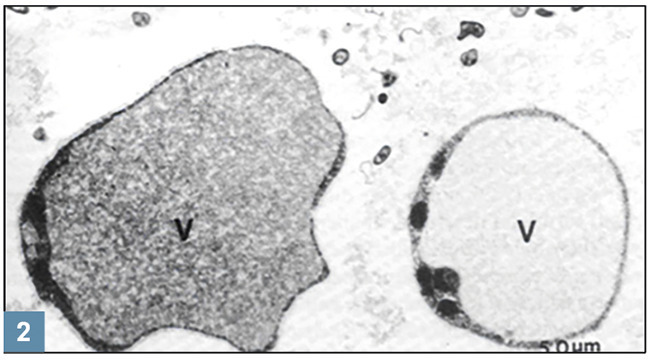

Ils ont la forme d’une sphère avec une grande vacuole qui repousse le cytoplasme en périphérie, aspect confirmé par la microscopie électronique : grande vacuole vide et cytoplasme périphérique contenant noyaux, mitochondries, appareil de Golgi, ribosomes et inclusions lipidiques (fig. 2 ). En microscope électronique à balayage : sphères à la surface rugueuse (fig. 3 ).

Ils ont la forme d’une sphère avec une grande vacuole qui repousse le cytoplasme en périphérie, aspect confirmé par la microscopie électronique : grande vacuole vide et cytoplasme périphérique contenant noyaux, mitochondries, appareil de Golgi, ribosomes et inclusions lipidiques (